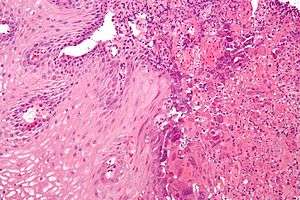

| Micrograph of herpes esophagitis. H&E stain. | |